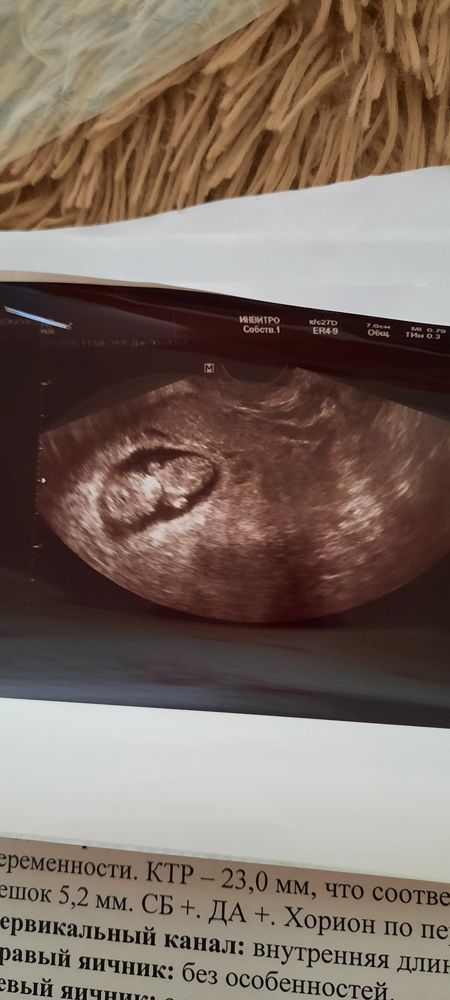

Миома при беременности

Изображение

Конечно же я не удержалась и сгоняла снова на узи)) по-быстренькому, чисто послушать сердце, убедиться, что все живы-здоровы. Тк без записи, не санкционированно, было неловко отнимать у врача много време